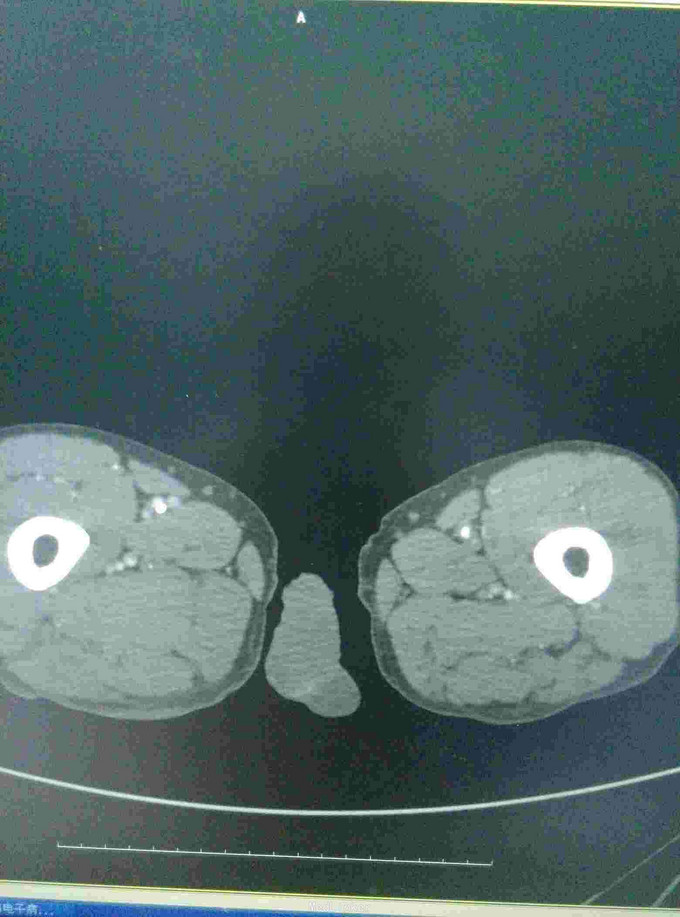

男患,74岁,间歇性跛行2年伴右足疼痛9+月,2年前无明显诱因出现间歇性跛行,行走后伴下肢远端疼痛、乏力,休息后缓解,无红肿发热及感觉异常,后行走距离渐变短,9月前加重伴远端静息痛。

左下肢皮温降低,左足背可见紫红色淤斑,左股动脉扪及微弱波动。下肢血管成像提示:双下肢动脉节段性不同程度狭窄、闭塞。

ASO是动脉粥样硬化引起的,好发于45岁以上男性,早期主要表现为间歇性跛行,晚起出现静息痛、缺血坏跙或溃疡。动脉造影有助于确定诊断,临床上可采用PTA,内膜剥脱术、旁路转流术等。